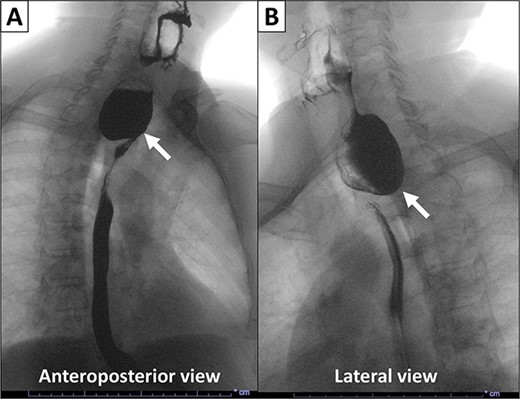

Gross examination revealed a fungating, exophytic, ulcerated, firm mass measuring 3.2 × 2.5 × 1 cm with a white cut surface involving the full thickness of the esophageal wall and grossly abutting the serosal surface. Microscopic examination showed a moderately differentiated SCC, invading the submucosa (Fig. 3). The surgical margins of resection were free of carcinoma and one cervical lymph node was identified and it showed no metastatic carcinoma. Postoperatively, the patient did well with no reported complications. An X-ray esophagogram was done showing no postoperative leak and no residual ZD (Fig. 4). He was referred to a hemato-oncologist for further management.

X-ray esophagogram performed postoperatively. No postoperative leak and no residual ZD were seen.